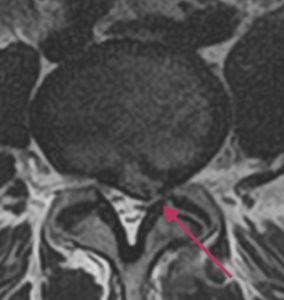

Lannerangan poikkileikkaus 1

Lannerangan aksiaalikuva (poikkileikkaus).

Magneettikuvauksen avulla voidaan nähdä selkäydinkanavan tilavuus ja hermojuurten vapaa tila. Poikkileikkauskuvista (aksiaalitaso) voidaan luotettavasti todeta mahdolliset hermopinnetilat, joita esimerkiksi välilevyn pullistuma voi aiheuttaa.